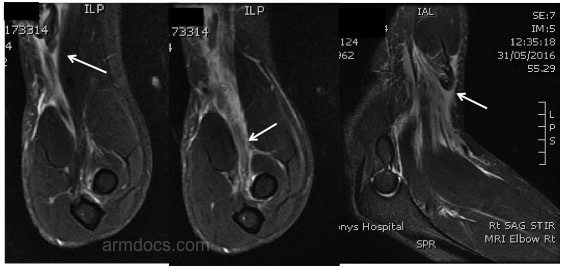

A diagnosis of biceps tendon tear is made based on the history of sudden pain and a snapping sensation on the front of the elbow whilst lifting a heavy object. This may be associated with a feeling of weakness. Examination in individuals with a complete tear of the tendon shows a change in the contour of the biceps muscle referred to as a reverse “Popeye” sign. There may be some bruising on the front of the elbow. In the injured elbow it is not possible to hook a finger around the biceps tendon at the elbow (a positive “hook” test). In individuals with partial tears the tendon may be felt at the elbow but will be tender on squeezing. An ultrasound or MRI scan may be requested if the diagnosis is in doubt.